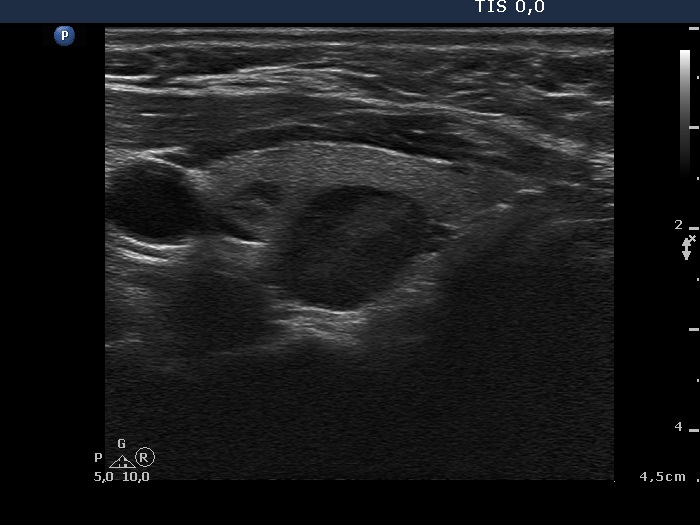

The operated thyroid - case 15 (ultrasonographic picture 7)

Left lobe, another longitudinal scan.